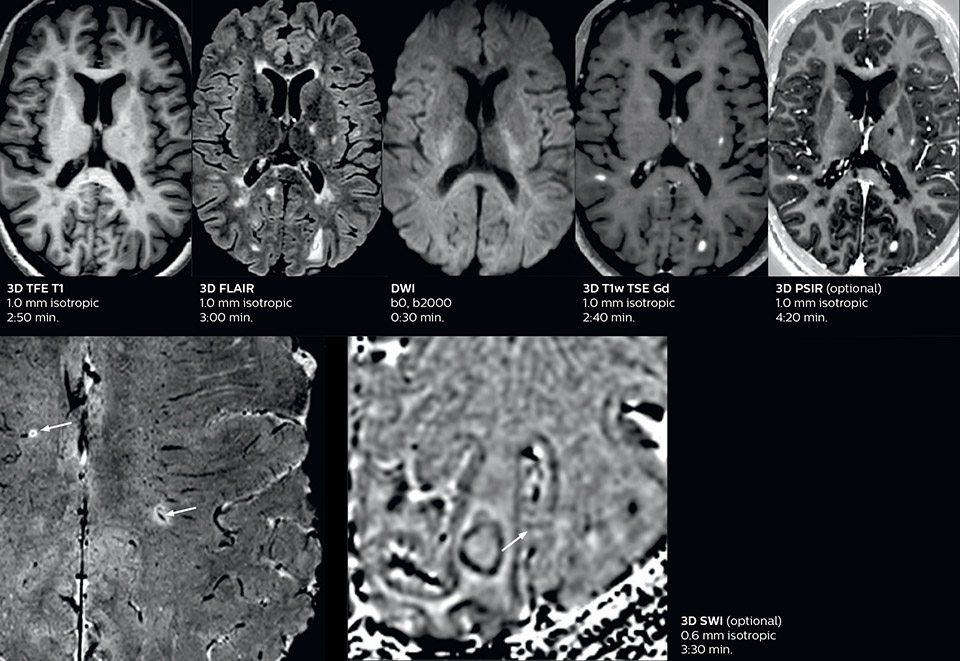

Fast acute stroke protocol

This is an example of acute ischemic stroke with distal occlusion of the right posterior cerebral artery. Note the improved visibility of the ischemic territory on the diffusion weighted image with high b-value. The 3D FLAIR shows a distal PCA occlusion. The fast SWIp depicts the thrombus on the isolated second echo image. The total scan time (including SmartBrain, preparations and a fast 3D T1w TSE Gd) is 8:00 minutes.

Fast acute stroke protocol A

Fast acute stroke protocol B